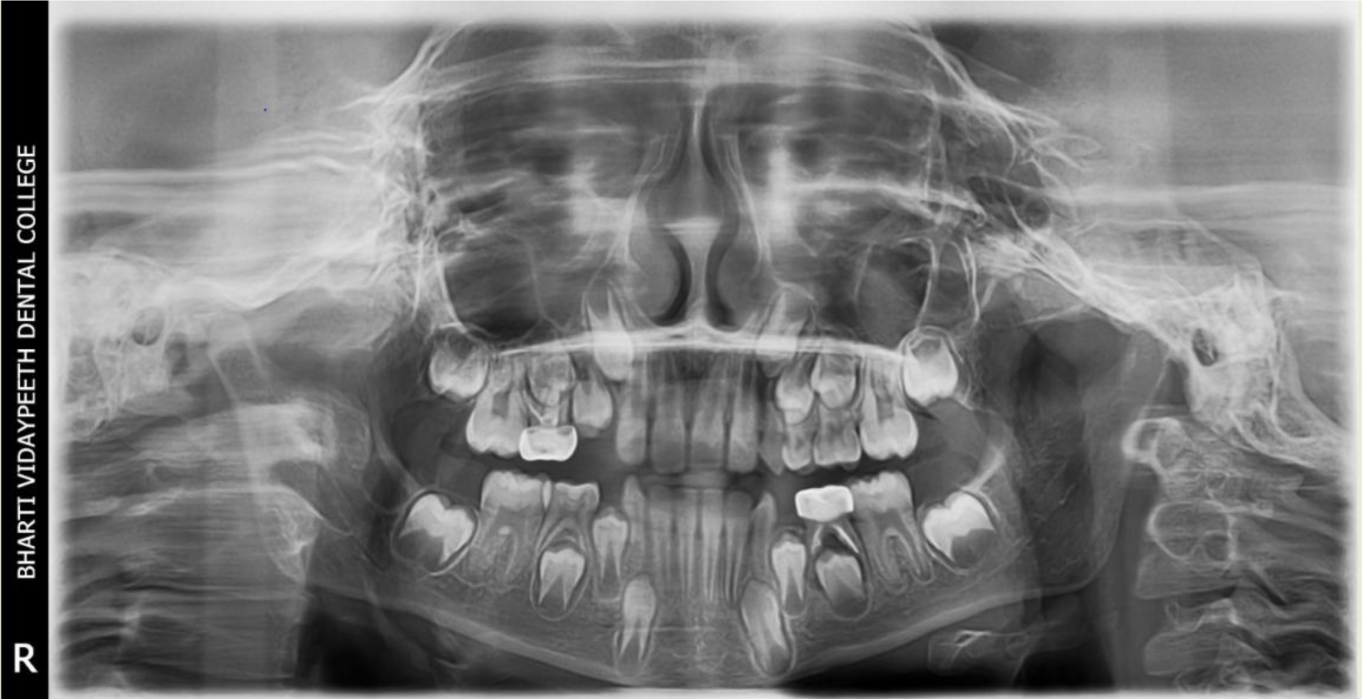

A nine year old boy reported to the Department of Pedodontics and Preventive Dentistry of Bharati Vidyapeeth Deemed University, Sangli with a chief complaint of pain and abscess in the lower left back region of the jaw since one month. Patient was a known case of autism spectrum disorder. He was inattentive, hyperactive and showed repetition of gestures. Psychological testing report showed childhood autism rating scale (CARS) 2, which falls into mild to moderate autistic category. Vineland social maturity scale (VSMS) measuring the social intelligence of child was found to be 31.5 with social age of around 5-6years. The family history was non-contributory. He was not on any medications and had reported no history of drug allergies. Extra-oral examination showed no specific findings (Figure 1). Intraoral examination revealed multiple carious lesions (Figure 2) (Figure 3). Occlusal caries involving enamel, dentin and pulp with 55 and 75. Intra oral dentoalveolar abscess was also seen in relation with 75 (Figure 4). Dentinal caries was seen with 85 and occlusal pit and fissure caries was seen with 65. No soft tissue abnormalities were appreciated. Radiographic evaluation by orthopantomogram was also done which revealed no abnormality (Figure 5). It was difficult for the patient to co-operate on the dental chair and understand the instructions given to him; hence treatment was planned under general anaesthesia. A complete pre anaesthetic evaluation was done and the patient was categorized under ASA II. Treatment plan was explained to the child’s parents and a written consent was obtained from them. The dental treatment done under general anaesthesia included pulpectomy of 55, 75 with glass ionomer cement restoration followed by placement of pre trimmed and pre contoured stainless steel crowns (Figure 6) (Figure 7). Glass ionomer cement restorations were done in 65 and 85 and pit and fissure sealants application on 16, 26, 36 and 46. Post-operative orthopantomogram showed well placed restorations and crowns (Figure 8). Patient’s post-operative recovery was uneventful. Treatment rendered reduced the pain and discomfort.Oral hygiene care instructions were given to the parents and maintenance protocol was explained and they were also encouraged for regular follow-up for preventive dental care. The two months follow-up revealed improved eating habits of the child.

Figure 5 Pre-operative orthopantomograph.